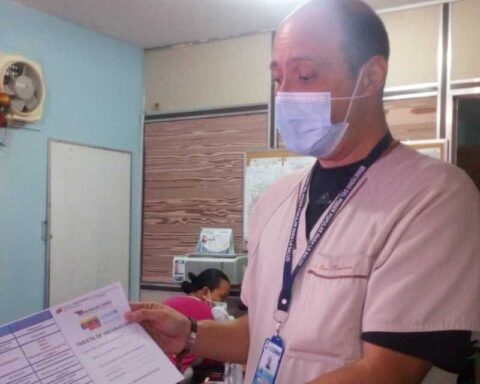

MoreA total of 23 cases of contagion of COVID-19 by community transmission were detected in the last 24 hours, raising the confirmed